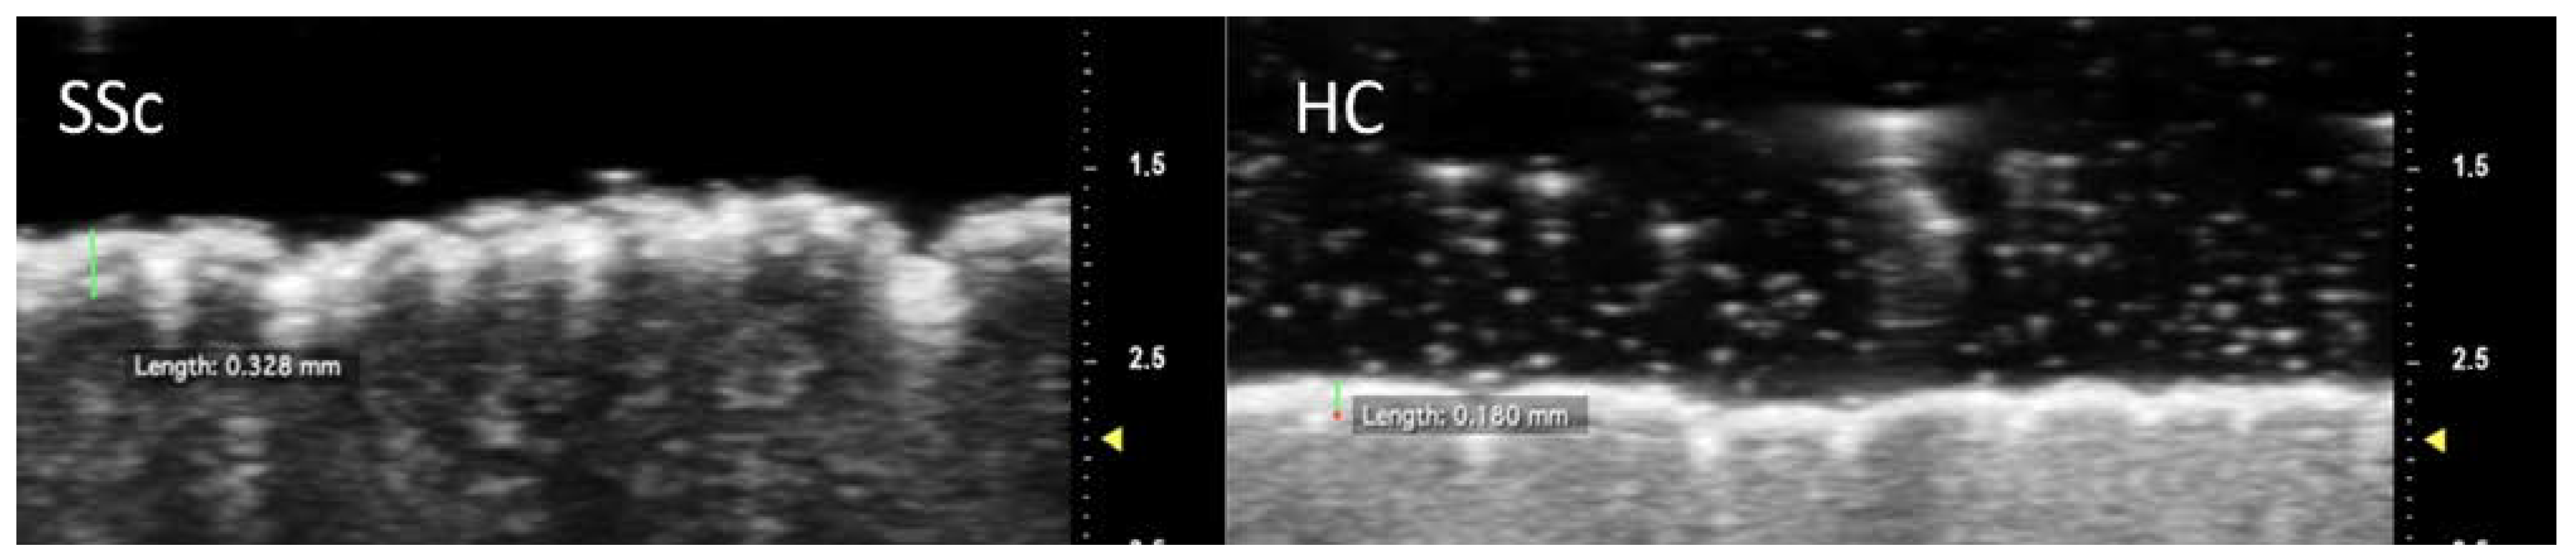

Figure 2.

Measurement of epidermal thickness at the intermediate phalanx of the second finger. Note the increased thickness of the epidermal layer in the SSc patient compared to the control subject.

The SSc group also presented lower epidermal MGV at DP, IP and PP (p = 0.01 for all). Similarly, low values of dermal MGV reached statistical significance at DP (p < 0.001), IP (p = 0.006) and PP (p = 0.04)—Figure 3. When UHFUS results were diversified according to skin subset, both lcSSc and dcSSc reconfirmed a significantly thicker epidermal layer than HC for all the regions of interest. Noteworthy, when considering MGV differences between cutaneous subsets and HC, statistically significant lower values were detected for both skin subsets only at the dermal layer of DP (p = 0.001 for lcSSc; p = 0.008 for dcSSc) and IP (p = 0.05 for lcSSc; p = 0.01 for dcSSc).

Measurement of epidermal and dermal grayscale values using ROIs positioned at the intermediate phalanx of the second finger. Note the reduction in the mean grayscale value in the SSc patient compared to the control subject in the epidermal and dermal areas.